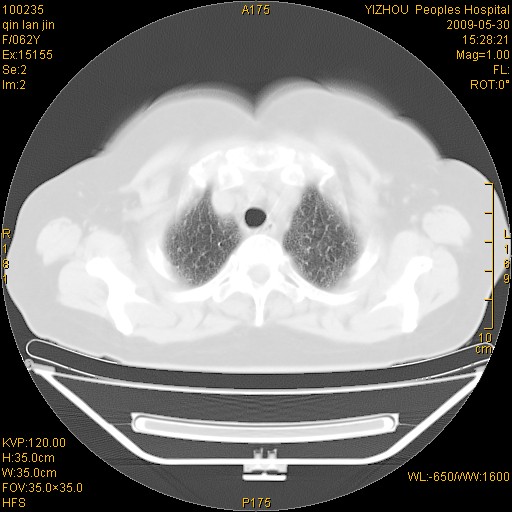

标题: CT20268:肺泡癌?间质性肺炎? [打印本页]

标题: CT20268:肺泡癌?间质性肺炎?

女,62岁,近二年经常咳嗽,近二个月,消瘦、乏力。

前面一张胸片是今天照的,后面一张胸片是去年9月份的。